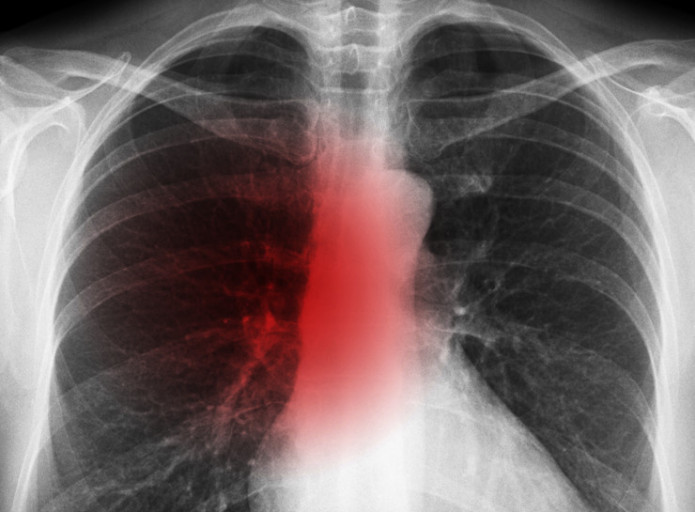

- 호흡 곤란 및 흉통

- 설명: 폐암 세포가 커지면서 기도를 좁히거나, 흉수(가슴에 물이 참)가 발생하면 숨이 차고 호흡이 곤란해집니다. 처음에는 운동할 때만 숨이 차다가, 병이 진행될수록 가만히 있어도 숨쉬기 힘들어집니다. 또한, 암세포가 흉벽(갈비뼈, 늑막)으로 전이되면 날카롭거나 둔한 흉통이 발생할 수 있습니다.

- 정기적인 건강 검진: 위와 같은 증상이 하나라도 나타나면 즉시 병원을 방문하여 흉부 X-ray, CT 촬영 등 검사를 받는 것이 중요합니다.